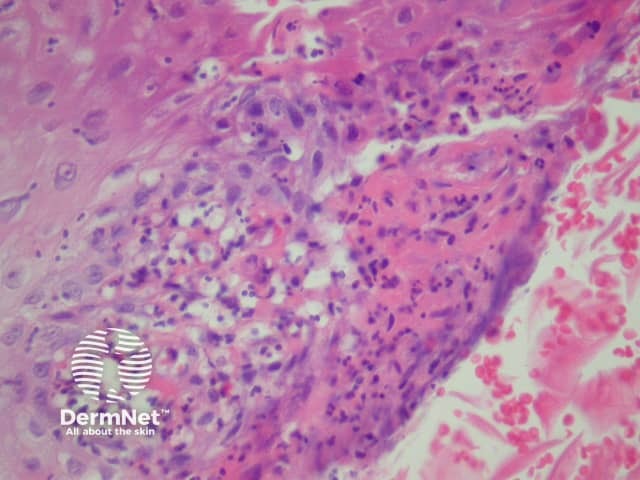

In blastomycosis-like pyoderma, sections usually show a broad verrucous lesion with epidermal papillomatosis which may resemble a keratoacanthoma (figure 1). There may be surface erosion and suppuration (figure 2). Numerous cystic spaces connect with the surface via draining sinuses (figure 3). There may be a pseudo-infiltrative growth pattern as the regenerative epithelium mimics an invasive squamous cell carcinoma (figure 4). Neutrophilic collections are present in the dermis and within squamous islands (figures 5, 6).

Figure 5

Figure 6